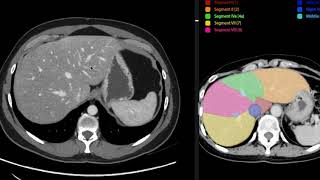

contraste incrementar el contraste o incrementará las diferencias entre los diferentes tejidos de acuerdo a la perfusión del órgano en esta imagen observamos un corte axial de abdomen en una tomografía sin medio de contraste en donde visualizar todas las estructuras no es muy simple sin embargo si administramos nosotros medio de contraste podemos observar con mayor diferencia la diferencia entre los tejidos vasculares por ejemplo aquí la aorta y los diferentes tejidos las imágenes no son 100% similares ya que se toman a diferentes niveles dependiendo la respiración del paciente pero noten como ya es posible identificar de una

manera más sencilla todos los órganos como vemos aquí el hígado la vena puerta y la vena cava inferior los riñones inclusive con su medular y su cortical el páncreas el vaso en este vídeo vamos a observar cómo podemos manipular nosotros las ventanas en esto que es una tomografía de tórax con medio de contraste en un recién nacido que tiene transposición de los grandes vasos vean como ahí vamos a observar todos los tejidos blandos con medio de contraste y vamos a seleccionar ventana o sea para poder ver los huesos donde podemos inclusive observar los núcleos de